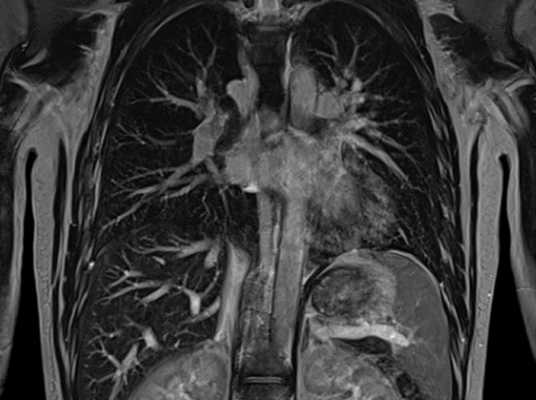

Магнитно-ядерная томография не очень информативна при исследовании костных тканей. Плохо видны на снимках и легкие, в которых слишком много воздуха. В процессе дыхания они двигаются, что не позволяет получить четкие изображения легочных тканей. Чтобы повысить четкость картинки, врач может попросить пациента во время сканирования периодически задерживать дыхание на вдохе. Та же проблема наблюдается при попытке проверить сердечную мышцу — ее ритмичные сокращения мешают обследовать миокард на патологии. Однако временно остановить сердце невозможно, поэтому оно фактически является единственным органом в груди, который проверяют с помощью так называемой синхронизации с пульсом/ЭКГ.

В медицинской практике МРТ грудной клетки делают, чтобы визуализировать следующие органы:

- плевру и ее полость;

- среднюю и нижнюю часть трахеи;

- легкие;

- перикард и сердце;

- диафрагму;

- лимфатические сосуды и узлы средостения;

- вилочковую железу;

- межпозвоночные диски грудного отдела позвоночника;

- спинной мозг в области грудного отдела позвоночника.

При использовании контрастного вещества список диагностируемых органов и структур расширяется за счет крупных и мелких кровеносных сосудов. С помощью этого дополнения МР-сканирование показывает не только строение кровеносной сети, но также особенности ее функционирования и изменения в скорости и направлении кровотока. Благодаря тому, что контраст хорошо накапливается в патологических новообразованиях, контрастное МРТ обладает высокой информативностью в диагностике опухолей органов средостения, включая легкие и лимфатическую систему.